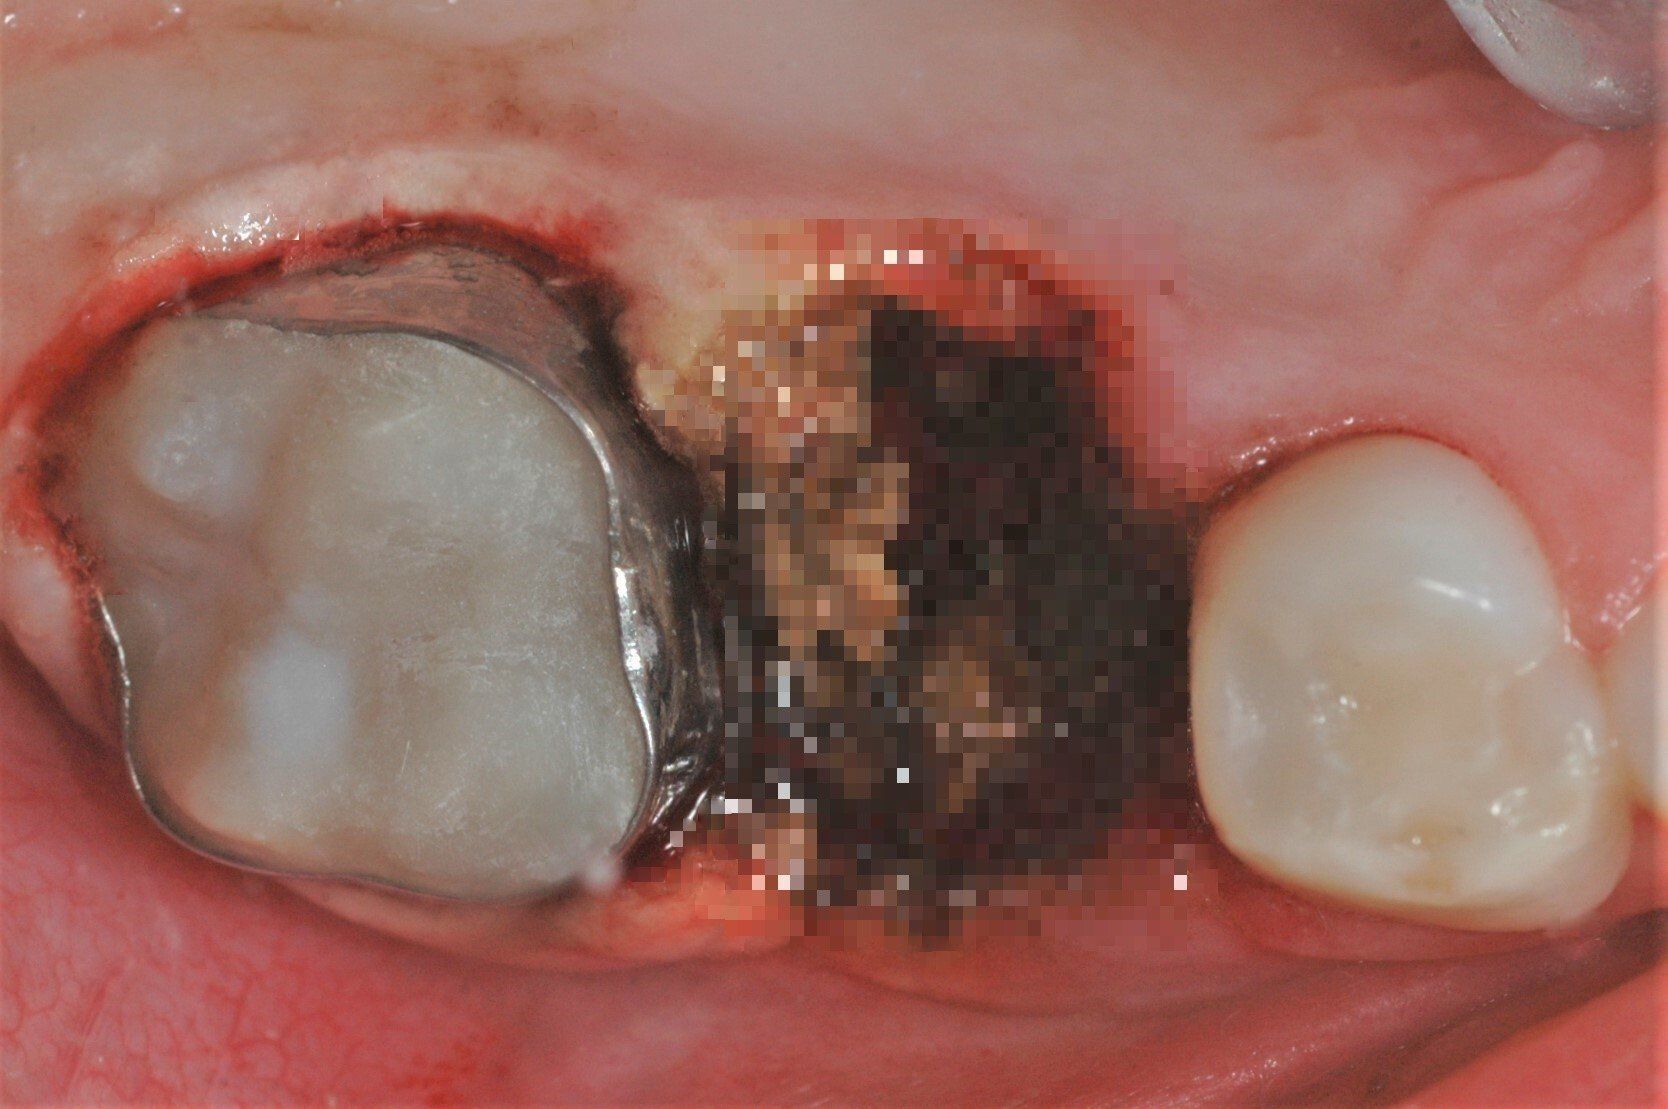

Bei Substanzdefekten, Karies und starker Empfindlichkeit sind Compositefüllungen und eventuell stützende Edelstahlbänder die beste Versorgung. Hier ein Fall aus unserer Praxis:

Passendes Molarenband vor dem Eingliedern

Fertig eingegliedertes Molarenband